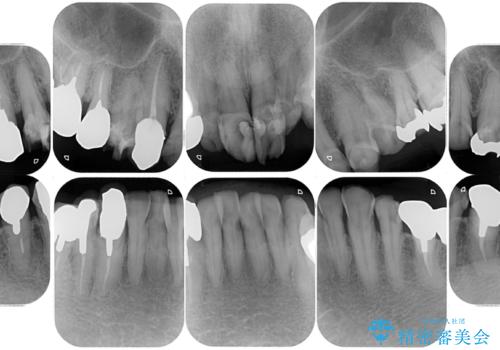

- 強い酸によって歯が広範囲にわたって侵食され、「歯がボロボロになった」と主訴に来院されました。詳細な診査の結果、重度の酸蝕症と診断。失われた歯質や咬み合わせの崩壊が著しいことから、単一の治療では対応が困難と判断し、矯正治療、インプラント治療、セラミック治療を組み合わせた総合的な治療計画を立案しました。矯正治療後に最終的にセラミックを用いて機能性と審美性を回復。患者様と綿密な話し合いを重ね、長期的な口腔内の健康維持を見据えた最適な治療を行いました。

酸蝕症の原因に関しては、医科のほうで解決済みでしたので、失われた機能、審美性の回復のため矯正治療によって歯並びと咬み合わせのバランスを整えセラミックによる修復を行ました。

保存できないと判断した歯は抜歯しインプラントにて治療をおこなっています。